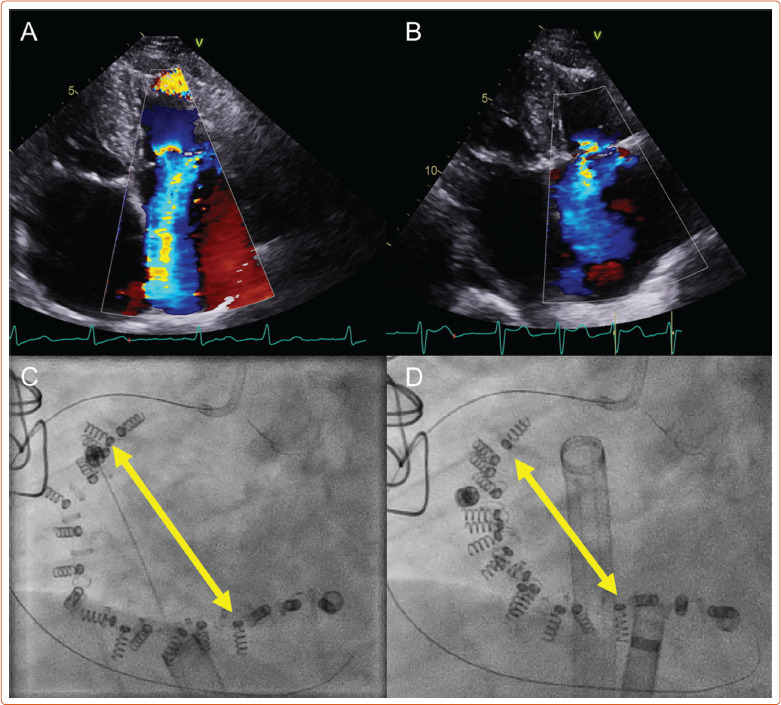

Abstract Image